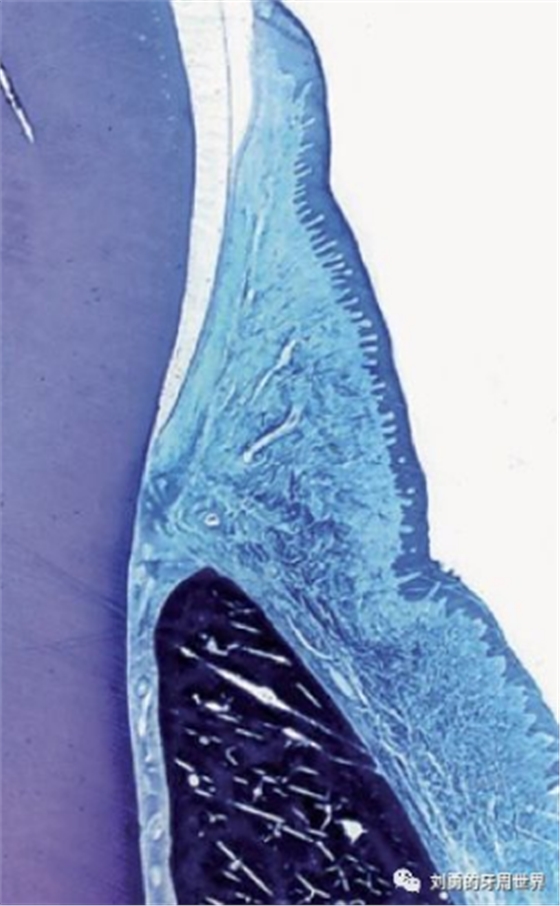

下面的這張切片也表明齦溝上皮是有釘突的。

但是再來看一張切片:

這張切片當(dāng)中,在齦溝上皮的區(qū)域似乎看不到明顯的釘突。